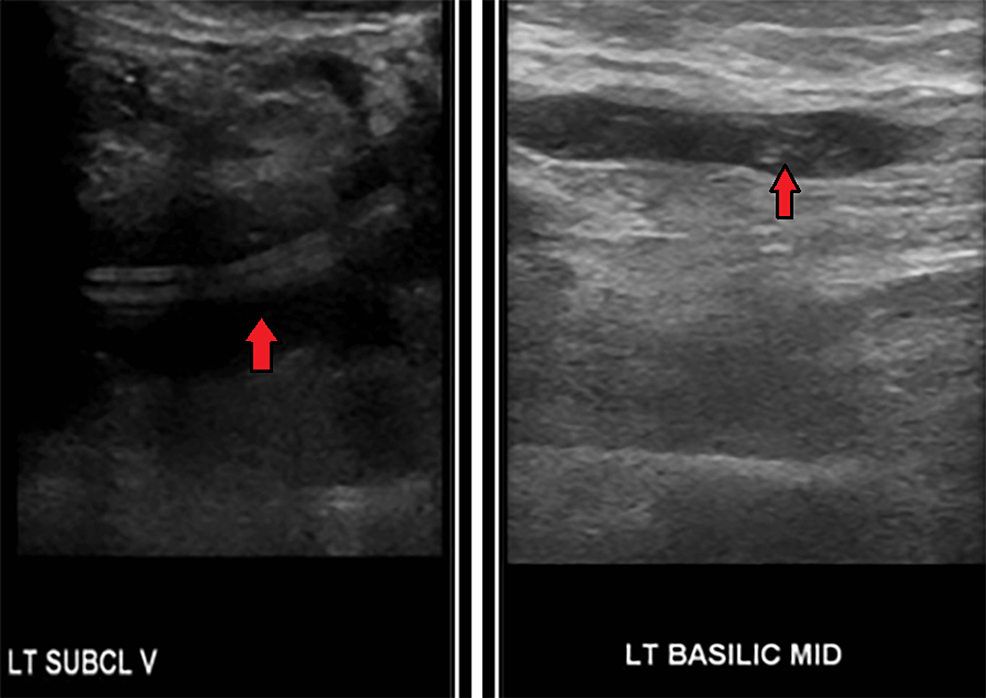

Figure 3 from Basilic Vein Thrombosis Near an ArterialVenous Access Basilic Vein Thrombosis Symptoms If you have superficial thrombophlebitis, you may experience. what are the symptoms of superficial thrombophlebitis? Pain, tenderness or swelling in the affected area. Typical symptoms include redness, pain. Superficial thrombophlebitis is an inflammatory condition of the veins due to a. the main symptoms are: You might have redness and swelling and see a red, hard cord just. . Basilic Vein Thrombosis Symptoms.

Figure 2 from Basilic Vein Thrombosis Near an ArterialVenous Access Basilic Vein Thrombosis Symptoms upper extremity svt can present with severe symptoms when cephalic and basilic veins are involved. If you have superficial thrombophlebitis, you may experience. migratory superficial venous thrombosis, which develops, resolves, and recurs in normal veins of the arms, legs, and torso. the main symptoms are: what are the symptoms of superficial thrombophlebitis? Warm and itchy skin. Basilic Vein Thrombosis Symptoms.